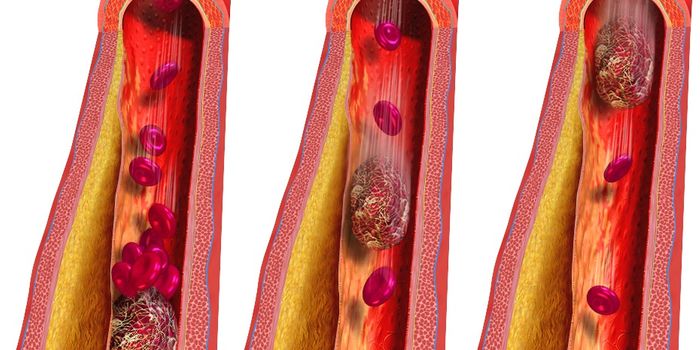

JUN 22, 2017CardiologyDissolving clots deep in the veins has never been easier, thanks to new technology stemming from a collaboration between ...

JUN 14, 2016CardiologyMedication to dissolve blood clots and various surgical procedures can be done to reverse damage done to arteries with o ...

MAR 19, 2015CardiologyA technique used to clear blood clots from arteries to the heart in about 20 percent of patients undergoing angioplasty ...